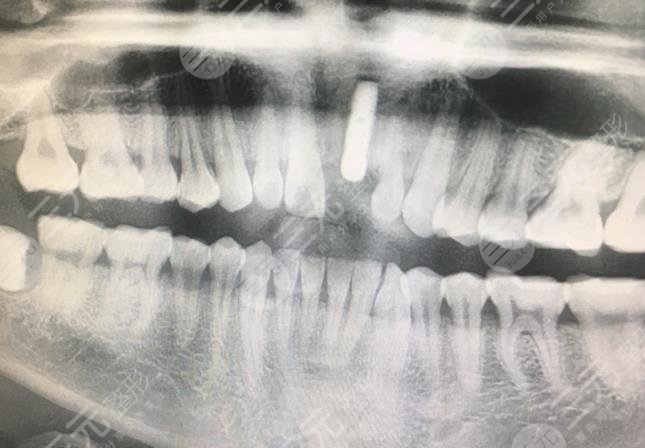

我是一名学生,因为平时在锻炼的时候可能不小心把牙齿磕掉了,一直想要去补牙,但是又害怕补的牙齿材料不好,导致牙齿脱落,所以说在朋友的介绍下就想要做牙齿种植缓解,后来也咨询了很多的牙科医院。在我们到地找到了一家知名度比较高的牙科医院做了牙齿种植。医生给我的感觉是较为专业的,而且也是较为有责任心的。在做牙齿种植的时候还对我的整个口腔情况进行了检查,因为医生告诉我只有在牙齿口腔健康的状态下才能够做牙齿种植,如果有牙周疾病是需要及时缓解的。

在做牙齿种植的时候注射了*药,所以说不会感觉到疼痛,这一点不用担心,但是*药失之后可能会有一些疼痛的,这种疼痛感可以忍受。我做完牙齿的种植大概需要4个月的时间,做完牙齿种植之后牙齿就恢复的比较好了,虽然说刚刚做完的时候,牙齿有一些肿胀还有出血的现象,但是没过几天就得到了好转,然后在差不多4个月的时候去医院安装了牙冠和剩下的缓解。

现在为止我做完了牙齿种植手术已经有半年多的时间了,感觉整个牙齿真的是恢复到了比较好的状态,不管是吃东西还是说话都已经较为自然了,做完的牙齿种植就跟我自己的牙齿一样自然根本就看不出是种植的牙齿。